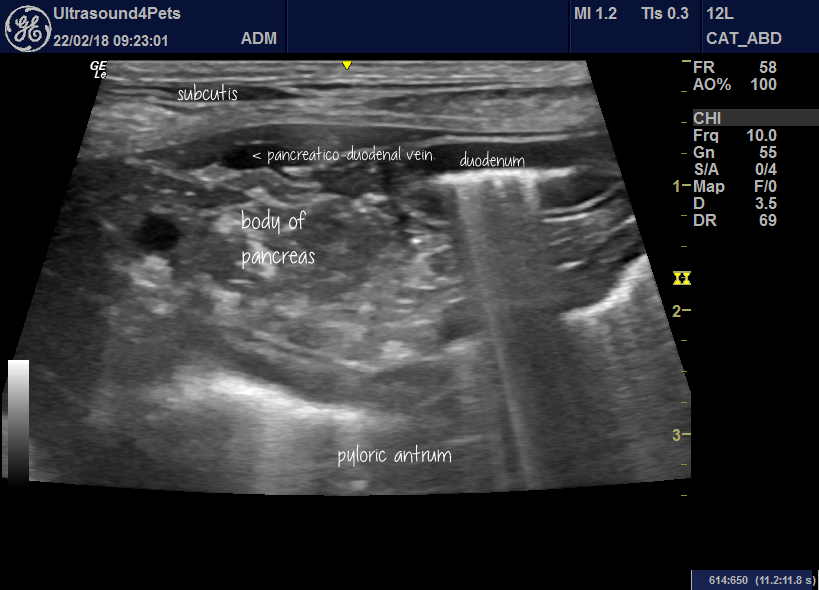

Ultrasound Characteristics of Canine Pancreatitis